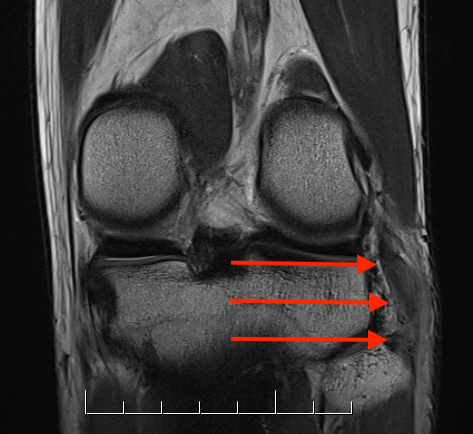

LCL

Harder to see on a single image. Need to scroll through coronal images

Coronal MRI with normal femoral insertion of LCL and popliteus

Coronal MRI of same patient demonstrating distal LCL avulsion from fibula